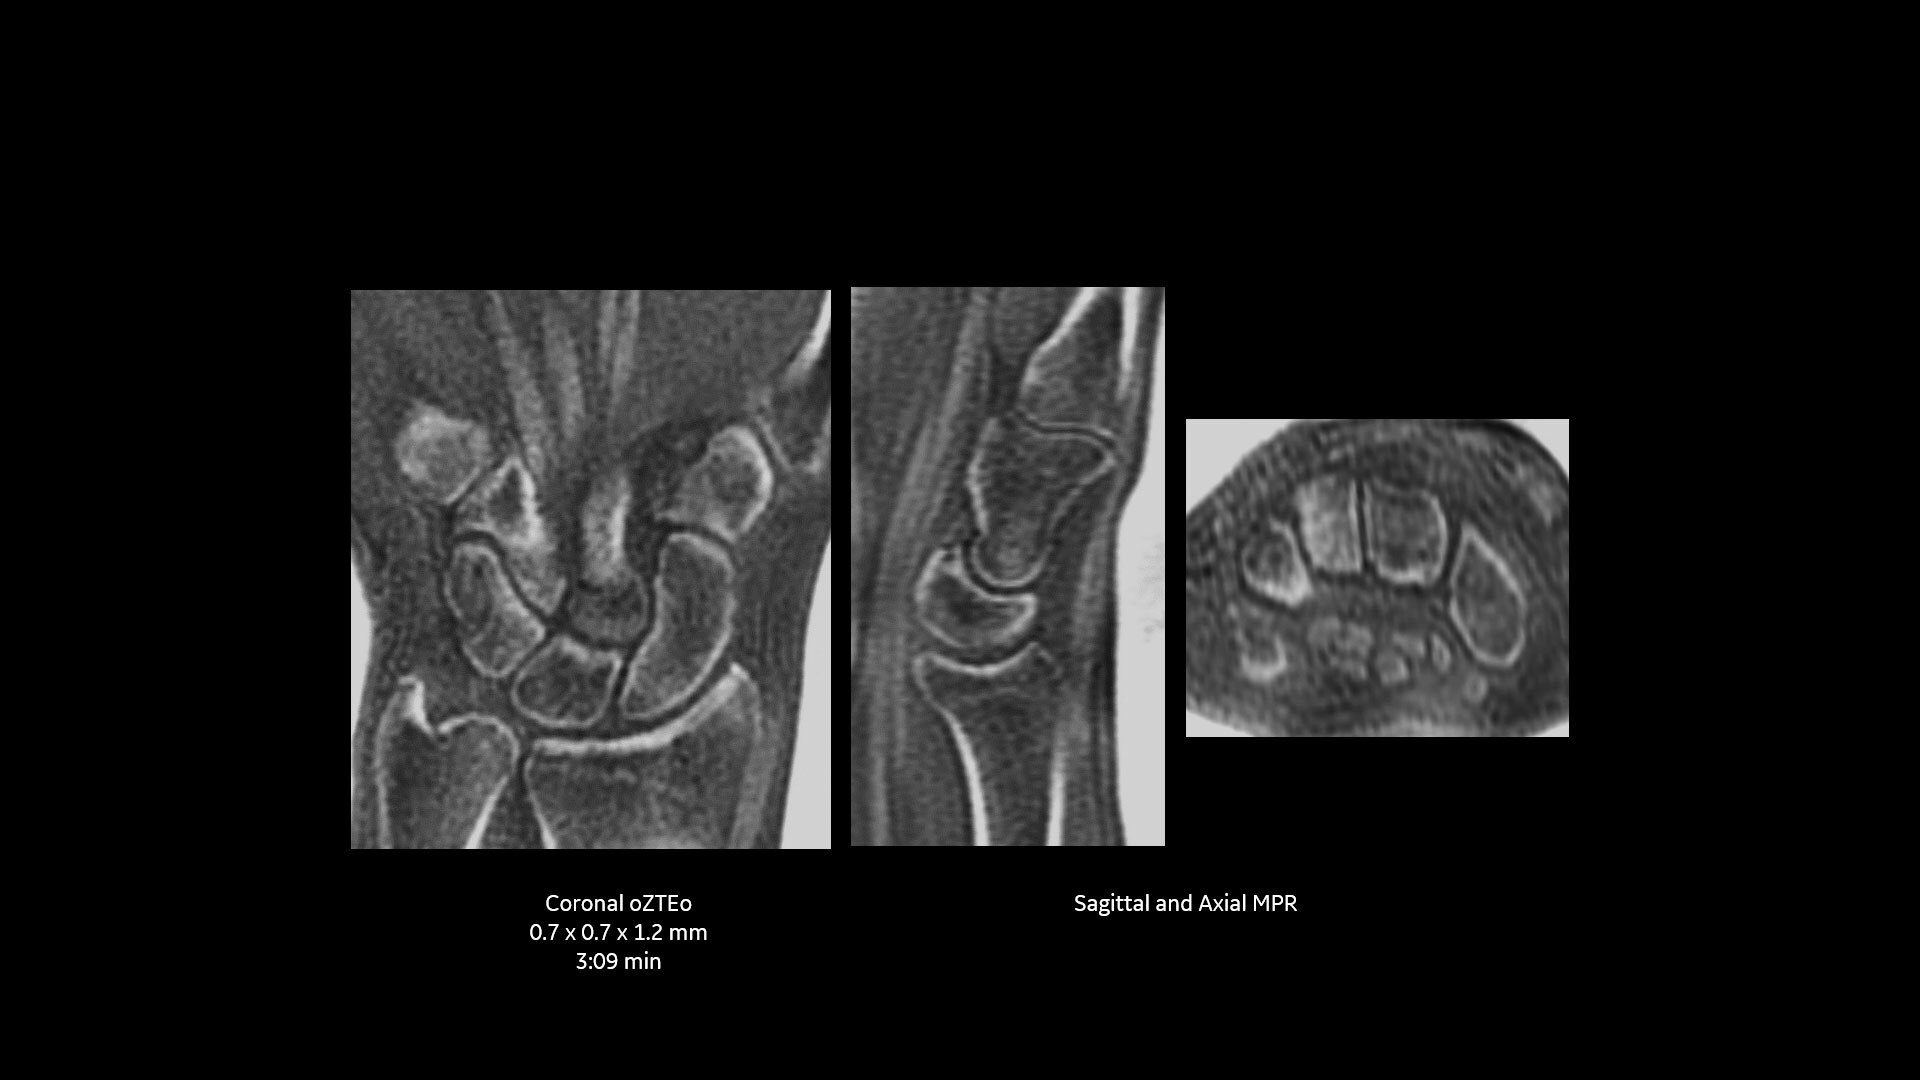

Powerful bone imaging for all anatomies

Available for all anatomies without ionizing radiation, oZTEo delivers images of bone morphology, calcification, ossification and fractures. oZTEo complements conventional MR soft tissue exams with perfect co-registration and provides 3D isotropic imaging using a radial ZTE acquisition, with inherent motion insensitivity. Use oZTEo with Volume Illumination for realistic 3D rendering.

When oZTEo is included in an MR exam, cortical bone information is perfectly co-registered with the soft tissue series, making it a one-stop imaging shop for most routine MSK needs.